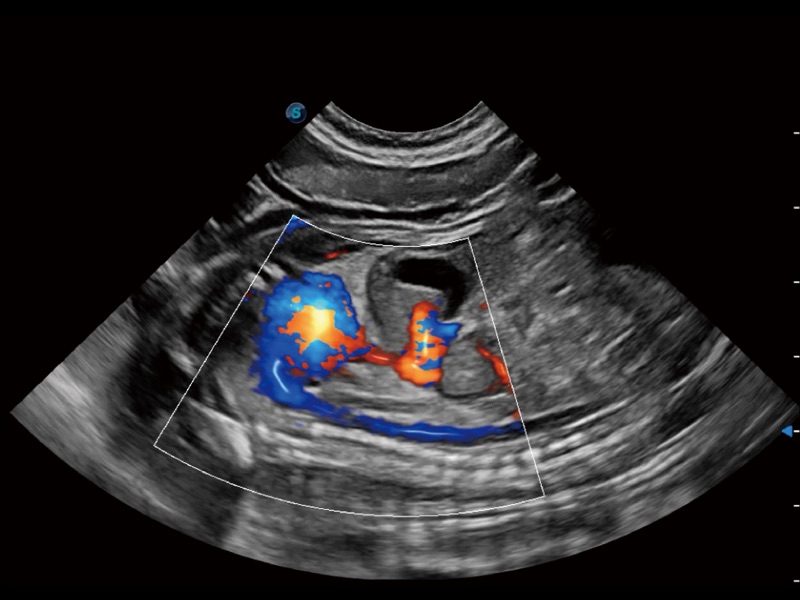

通过360度任意调节3条M型取样线,在同一心动周期上观察心脏不同位置的运动曲线,得到准确的心功能测量数据,有效评估心肌运动及左心室功能。

实时用颜色表示心肌组织运动,观察和定量组织的运动情况,对快速检测与评估心肌的灌注和活性、电传导及心肌收缩和舒张功能等均能提供重要的诊断信息。